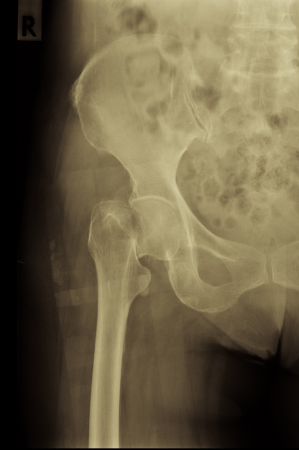

The HEALTH trial brought together an international team to address a long-standing question in femoral neck fracture care: whether total hip arthroplasty (THA) offers meaningful advantages over hemiarthroplasty. Investigators emphasized the scale, methodological rigor, and global collaboration behind the study. The results showed no meaningful difference in secondary procedures at two years, only modest functional gains with THA, and a higher rate of serious adverse events and dislocations. Contributors noted that the findings challenge previous assumptions, support hemiarthroplasty for most displaced fractures in independently ambulatory adults, and may shift practice toward a more balanced, evidence-driven approach.